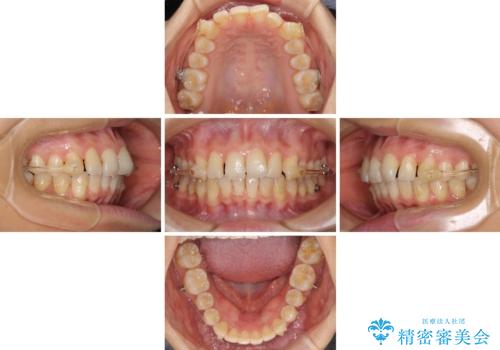

インビザラインによる矯正治療 カリエールディスタライザーを用いた奥歯の咬み合わせ改善

- 前歯の叢生と口元の閉じにくさを気にして来院された患者様です。

奥歯の咬み合わせを見ると、上顎が下顎に対して相対的に前方にありました。

口元の閉じにくさを改善するためには、上顎臼歯を後方に移動させた咬み合わせにする必要があります。

インビザライン単体で改善することも可能ですが、達成する可能性が高くないため、カリエールディスタライザーという補助装置を併用して、より確実性を上げることとしました。

奥歯の咬み合わせを改善しながら、並行してインビザラインで歯列を整えることとしました。

カリエールディスタライザーを併用したことで、確実かつ短期間で治療を終えることができました。